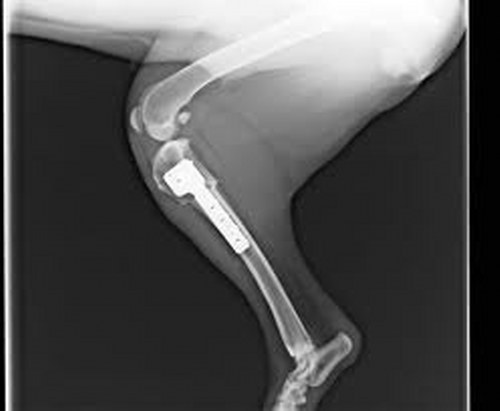

El objetivo de las sesiones es facilitar al veterinario el diagnóstico preciso a través del establecimiento de unas pautas consensuadas de exploración de los pacientes con problemas traumatológicos y ortopédicos. En este sentido, el director de AVEPA, Joaquín Aragonés, afirma que "durante las jornadas se revisarán los signos radiográficos y las manifestaciones clínicas para establecer las mejores opciones terapéuticas médicas y quirúrgicas".

Entre los temas más interesantes del programa destaca el diagnóstico de cojeras y problemas que afectan a perros y gatos y por ello, según Joaquín Aragonés "en las formaciones se proporcionará un enfoque diagnóstico global del paciente con casos prácticos y actualizados que aporten al clínico la información necesaria". Desde marzo hasta noviembre se desarrollarán 40 sesiones en toda España, en las que Boehringer Ingelheim colabora en la especialidad de traumatología.